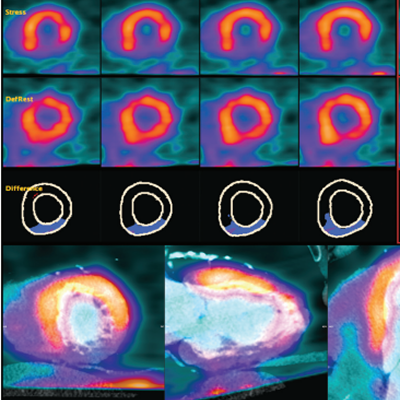

Quantitative Analysis for Cardiac PET and SPECT

Automated perfusion and viability difference imaging

Polar plots (with 17, 19, and 20 segment models), reversibility, and Z-score maps

Robust deformable image segmentation

Accurate template-based alignment to the left ventricle